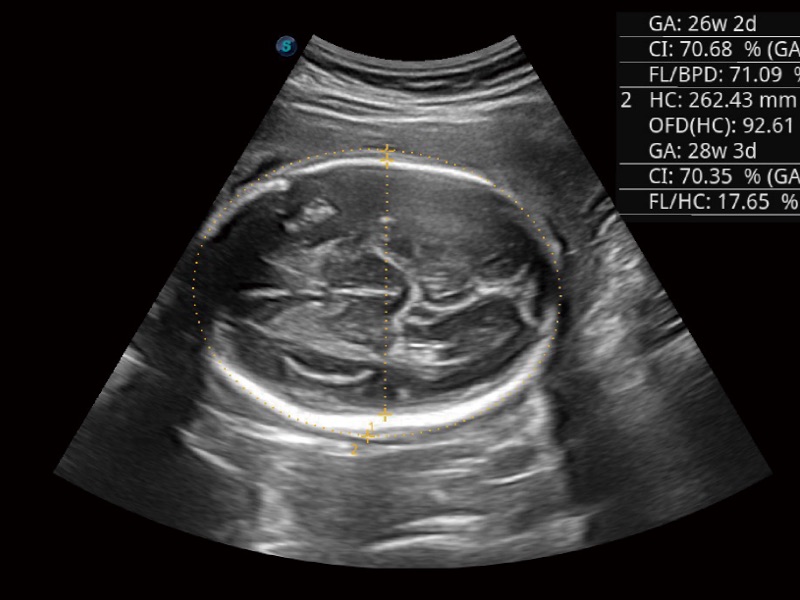

妇产科应用

三维光影成像技术采用新型的渲染方式,增强边缘信息,使得轮显示清晰完整,为临床提供丰富、直观的三维结构,提供临床诊断准确性。